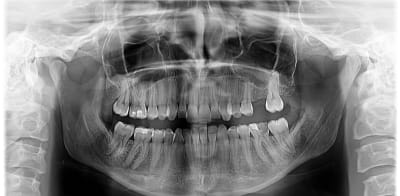

Resultat de mon endo

Lime endomoteur casse MV :s

Et finalement en distal c'était surement de l'hydroxyde de calcium car ça a plus ou moins disparu !!

(2seances d'hydroxyde de calcium, chaque seance irrigation Hypo, toujours sous digue, d'où la décision de laisser la Lime en place, la patiente est informée et rassurée)

Obturation composite direct